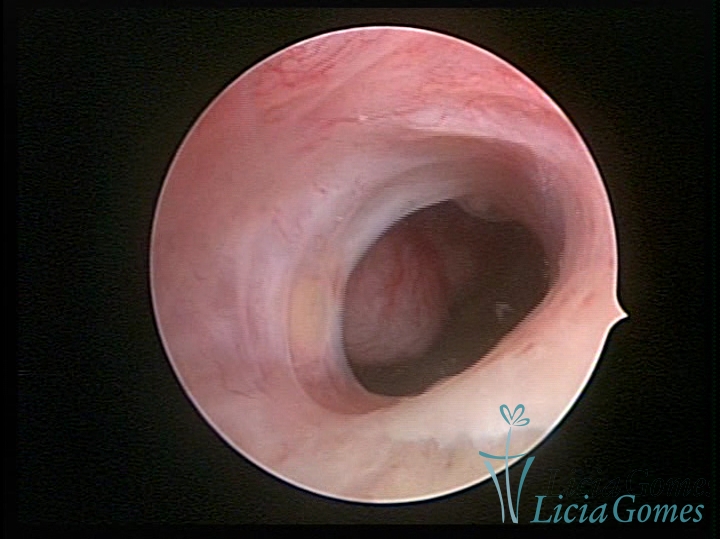

FIBROUS SYNECHIA

Uterine synechiae are scars (adherence) between the surface of the uterine walls, which may occur after the surgical procedure, uterine curettage, or after an inflammatory process in the uterine cavity (endometritis), which may lead to menstrual changes, infertility and obstetric complication such as abortion and premature birth.